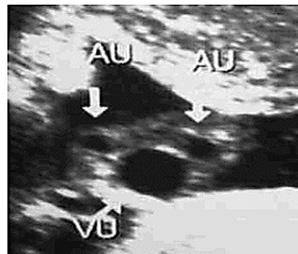

Figura 18. El cordón umbilical Corte transversal del cordón umbilical a la ecografía donde se evidencia el “Signo de Mickey Mouse” (AU: arteria umbilical, VU: vena umbilical)